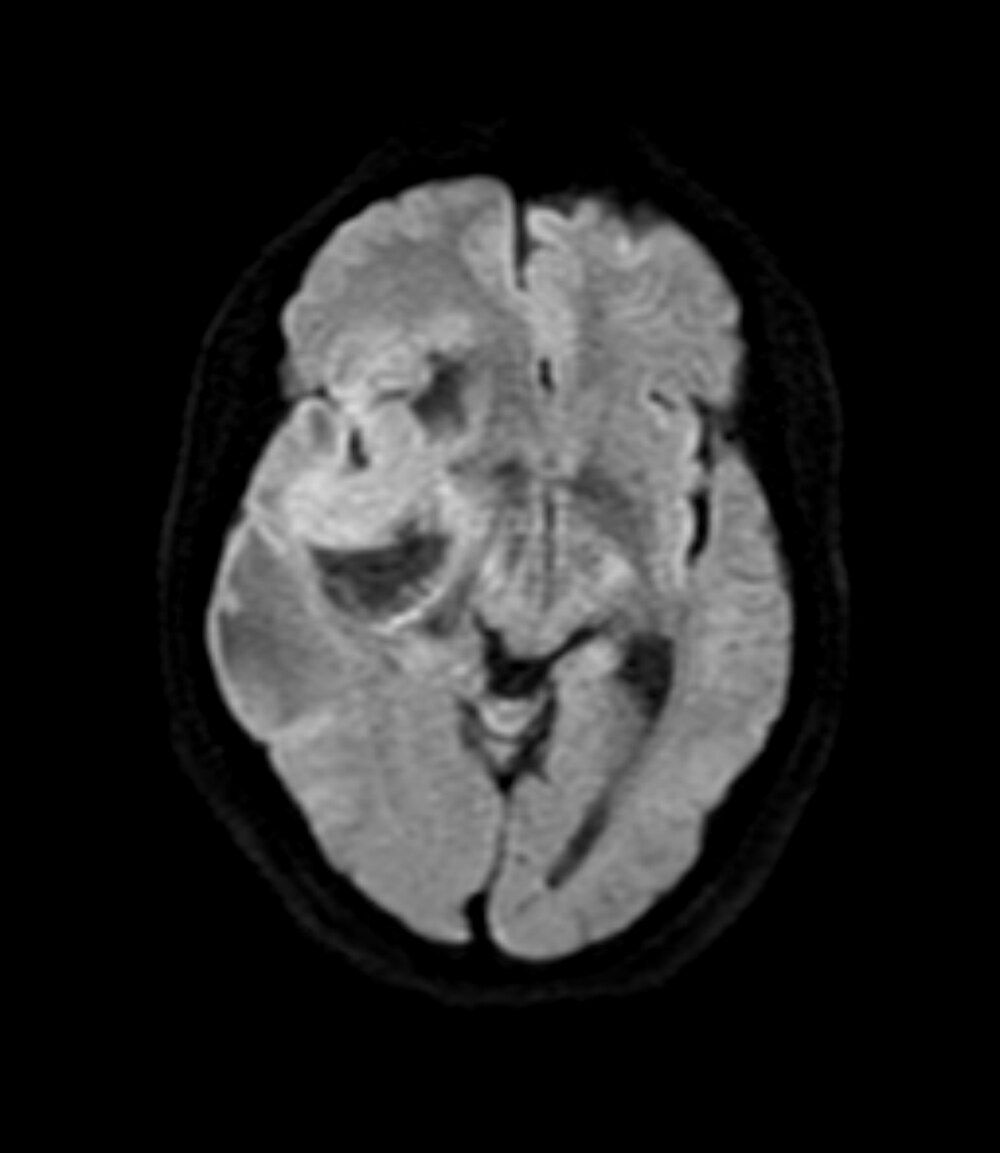

| DWI Ax b= 1000 | EPI | 0:40 | 5000 | 87.8 | ー | ー | 1000 | ー | ー | 2 | 2 |

| DWI Ax b= 1000 | 220 | 1.72*1.38 | RL 128 | AP 160 | 6 | 1.5 | 19 |

2週間前からの頭痛にて前医を受診し、CTで頭蓋内腫瘤や脳浮腫を認めたため、当院へ救急搬送された。当院で施行された造影MRIでは右側頭葉~前頭葉に約7.5×4cmの辺縁不整な腫瘤を認め、膠芽腫が疑われた。その後手術が施行され膠芽腫の診断に至り、手術後は化学放射線治療が施行された。

受診当日に施行されたCT/MRIにて偶発的に腫瘤が発見された。非造影のCTやT1強調画像、T2強調画像、拡散強調画像などでは腫瘤の存在や輪郭が不明瞭であることも多く、本症例のように造影を行うことで腫瘤の詳細な評価が可能となる。一般的には転移性脳腫瘍や脳膿瘍などが鑑別となり、その他のシーケンスや体幹部の所見、臨床データなどとも併せて診断を行うことが重要である。